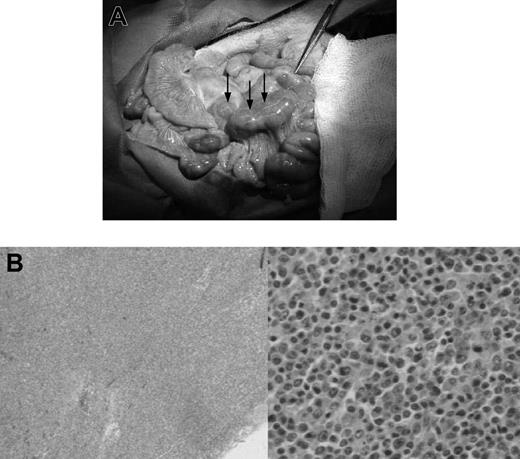

In animals with lymphoma or PTLD, mild hepatosplenomegaly and diffuse lymphadenopathy that included prominent enlargement of mesenteric lymph node chain were observed at autopsy (Figure 1A). This lymphadenopathy, in some cases, also included significantly enlarged lymph nodes in the neck and inguinal regions of the animal. Lymphoid tissues had histologic evidence of atypical cells and destruction of normal architecture (Figure 1B). Animals with leukemia had less significant lymphadenopathy and greater hepatosplenomegaly, with firmer and paler organs (Figure 2A). Lesions 0.5 to 1 cm in diameter were commonly found on the liver of animals with leukemia. Pleural effusions and ascites were not uncommon in these animals. There was also histologic evidence of diffuse infiltration consisting of large, pleiomorphic malignant cells containing heterochromatic nuclei. These cells were present throughout all vascularized tissues such as the kidney and the lung, and they were also prominent in the bone marrow (Figure 2B).

Gross pathologic and histologic findings of leukemia in miniature swine. (A) The most consistent findings of animals with leukemias were enlarged liver and spleen, which on palpation were firm and pale in color with visible lesions, as shown by animal 15549. Image was acquired using a Kodak camera (Eastman Kodak) model Easyshare Z740 with a 45.5-mm to 55-mm lens adapter. No further image processing was done. (B) Bone marrow from these animals was predominantly populated with abnormal cells, as represented by tissue from animal 14736. Slide was viewed with an Olympus BX51 compound microscope (Olympus America) of sections stained with H&E (Hematoxylin Gill's Formulation no. 2, Fisher Diagnostics; Eosin-Y, Richard-Allan Scientific) using a lens at 400×. Image was acquired using an Olympus digital microscope camera (Olympus America) model Q-Color 3, and was processed with Adobe Photoshop CS version 8 software (Adobe Systems).